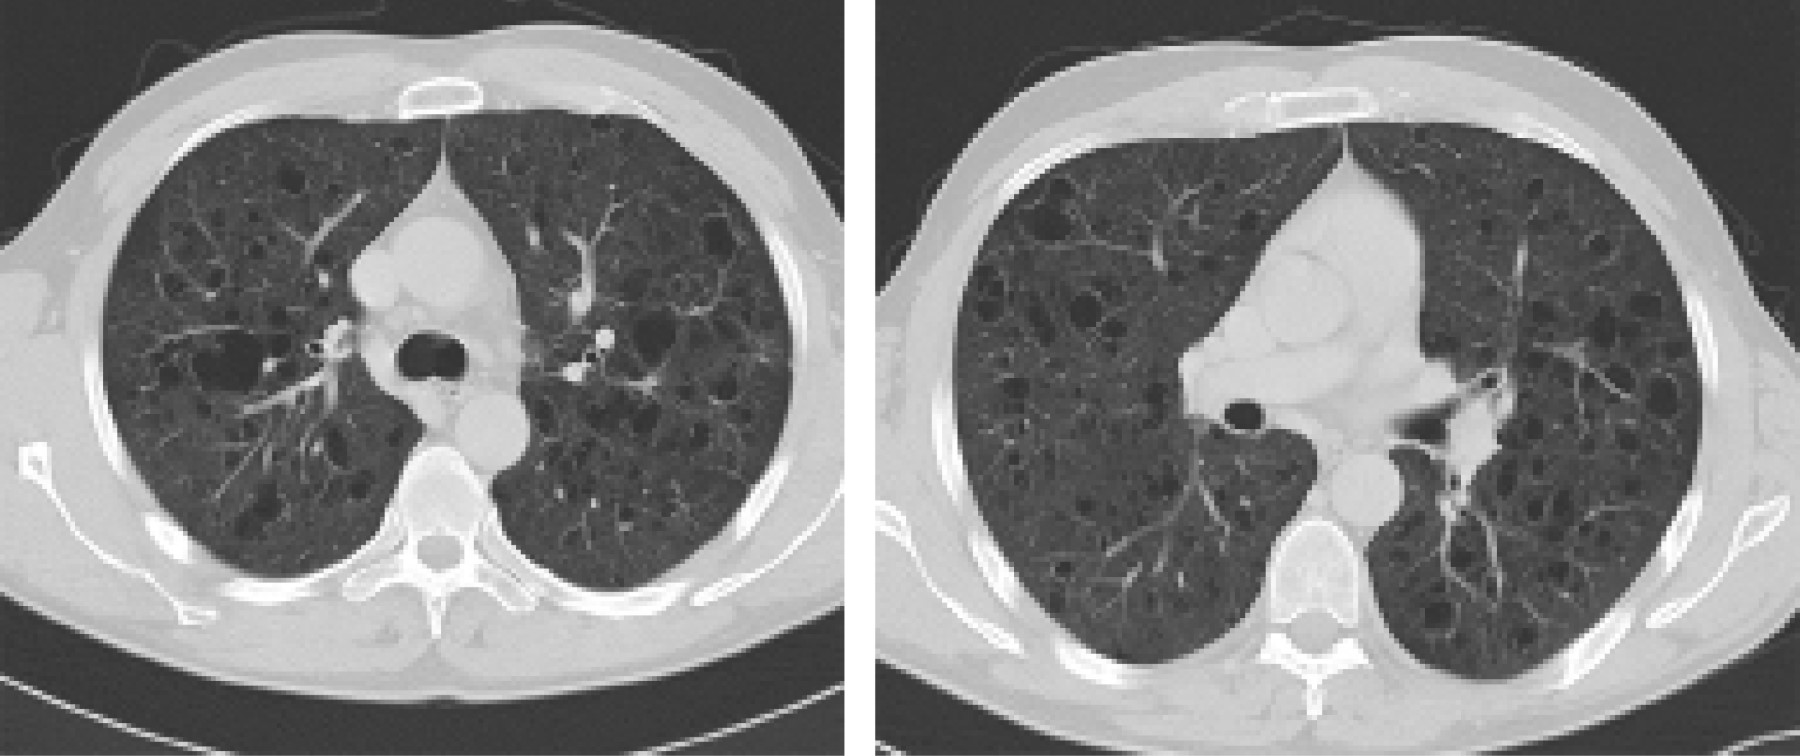

Se decidió realizar una tomografía computarizada (TC) para la valoración de otras posibles lesiones asociadas. El estudio puso de manifiesto de manera incidental la existencia de numerosas estructuras quísticas de paredes mal definidas con clara predominancia en ambos lóbulos superiores, asociando pequeños nódulos de distribución centrolobulillar. Los hallazgos radiológicos son sugestivos de enfermedad de histiocitosis de células de Langerhans pulmonar (Figuras 1 y 2).

La tomografía computarizada de alta resolución (TACAR) ha facilitado y proporcionado una mejor valoración del parénquima pulmonar. El patrón radiológico principal es la existencia de nódulos centrolobulillares de predominancia en lóbulos superiores y de tamaño inferior a 1 centímetro. La progresión de las lesiones quísticas en la TC se correlaciona con un mayor deterioro funcional pulmonar.6

Figura 1